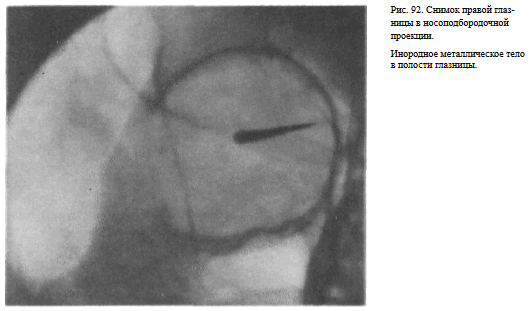

На прицельном снимке каждой из глазниц в этой же проекции, как правило, небольшие изменения структуры стенок, а также мелкие инородные тела глаза видны лучше. Такие снимки широко используют в офтальмологической практике (рис. 92).

Назначение снимка — изучение контуров костей, образующих вход в глазницу, структуры верхней и наружной ее стенок, ширины и контуров верхних глазничных щелей, а также выявление инородных тел в полости глазницы.

Укладка больного для выполнения снимка, информативность снимка, критерии правильности технических условий съемки и правильности укладки те же, что для снимка крыльев клиновидной кости и верхних глазничных щелей.

В качестве примера информативности снимка глазниц в носолобной проекции для выявления инородных тел глаза и деструктивных изменений стенок приводим два наблюдения.

Одно из них — случай ранения глаза металлической стружкой (рис. 93), другое — случай деструкции верхненаружного края глазницы при доброкачественной опухоли слезной железы (рис. 94).